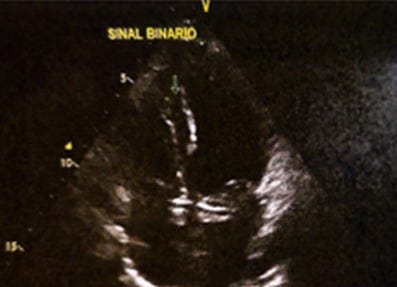

Imagem da semana

Imagem de ecocardiograma de paciente com Doença de Fabry, na qual observamos a presença do Sinal Binário, ou seja, um endocárdio hiperecogênico com uma camada subendocárdica adjacente hipoecogênica.

Apesar de sensibilidade e especificidade limitadas, é um achado, que junto ao aumento da espessura miocárdica e do papilar no ecocardiograma, alterações eletrocardiográficas, e redução do Mapa T1 com realce tardio inferolateral na ressonância magnética, pode nos auxiliar no quebra-cabeça das cardiomiopatias.